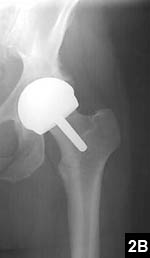

An uncommon, but useful indication for hip resurfacing is for patients with proximal femoral deformity, in whom a total hip can be difficult if not impossible (Figure 1). More commonly, suboptimal anatomy is an issue, as with patients in whom even the smallest stem requires reaming, which puts patients at long-term risk for stem fracture (Figure 2). Conversely, a large canal presents problems for implanting a cementless stem (Figure 3).

Figure 2: Preoperative templating of a 38-year-old dancer reveals the smallest standard stem available would still require reaming of cortical bone (A). Postoperative radiograph shows successful hip resurfacing was performed without entering the femoral canal (B).